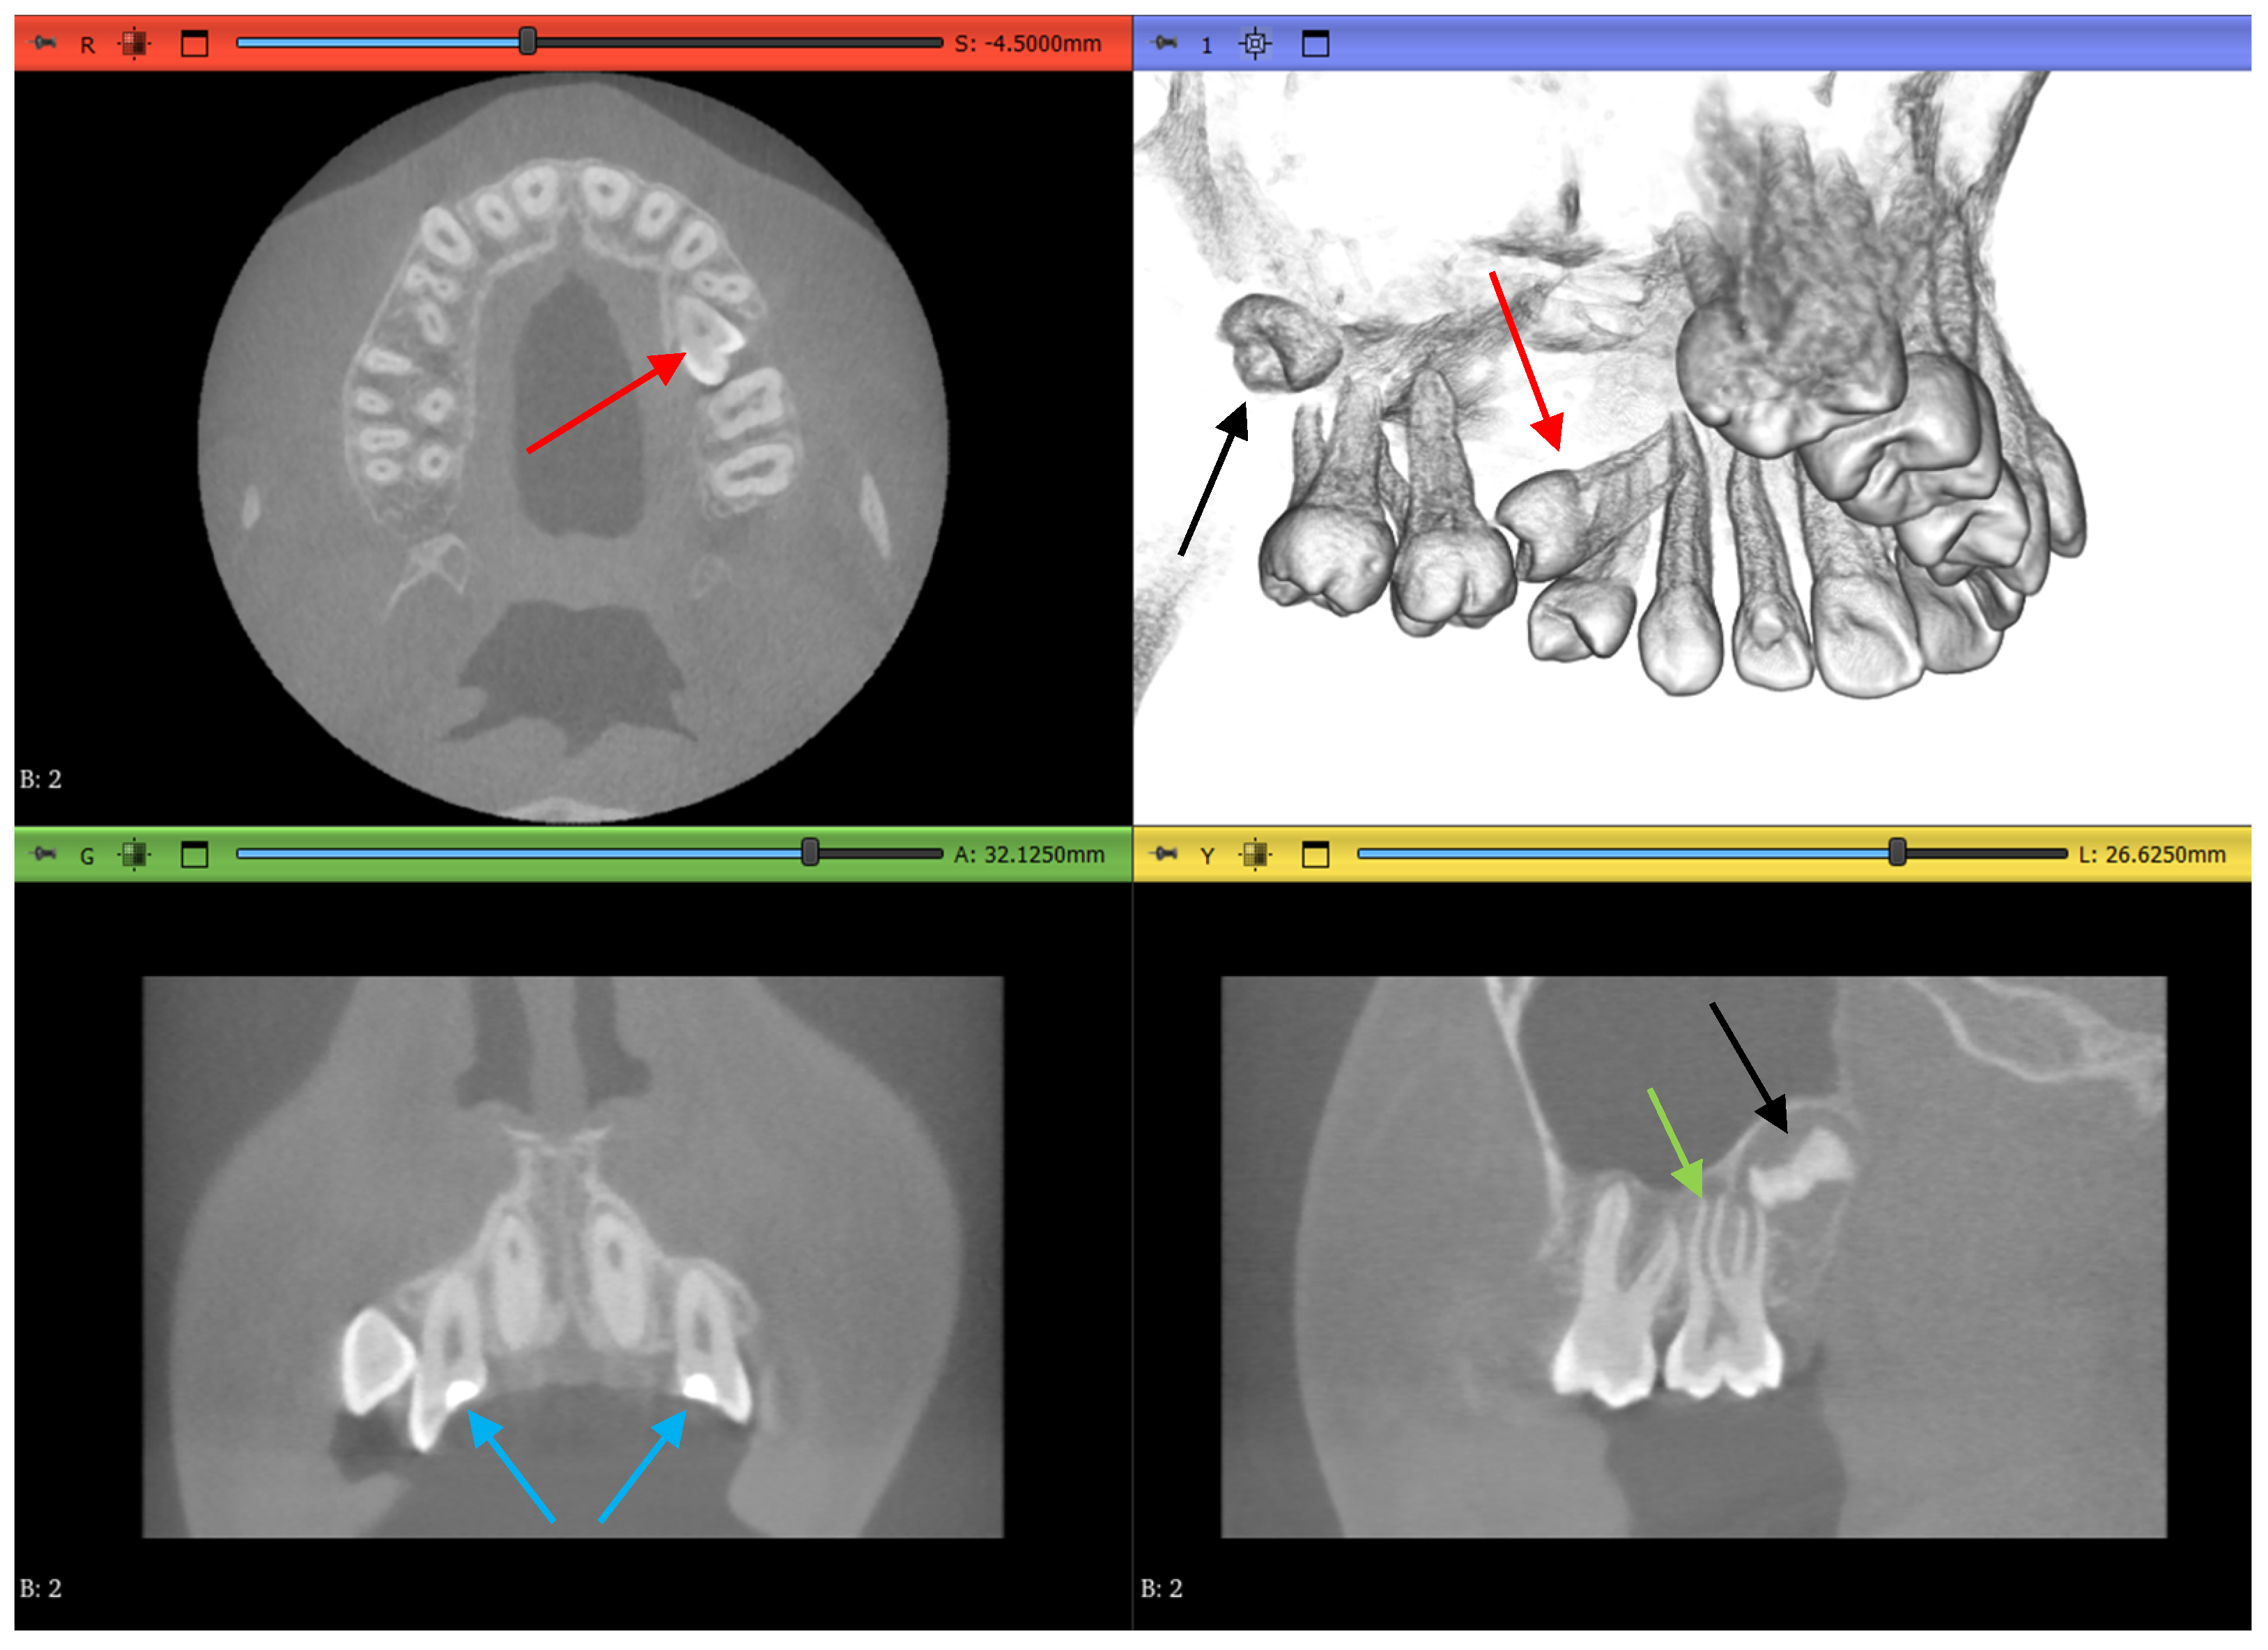

2.3.1. Volume Cropping

2.3.2. Histogram Adjustment

2.3.3. Thresholding Masking